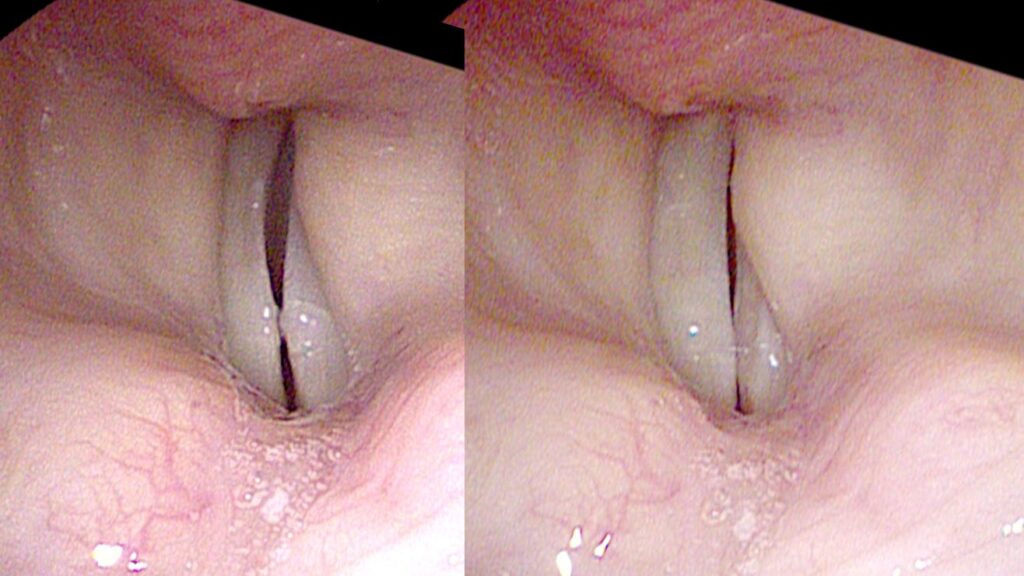

Timing Gap

Anything that makes the vocal cords uneven — in mass, length, or tension — can put them out of sync. With a mild asymmetry, they may oscillate out of phase. Under a strobe light it looks like they are chasing each other. They may never touch, so air continuously leaks out even while crossing each other’s path. This is a gap created by timing. If they become slightly more asymmetric, they may begin to oscillate at different frequencies — diplophonia — and both huskiness and roughness are heard simultaneously.